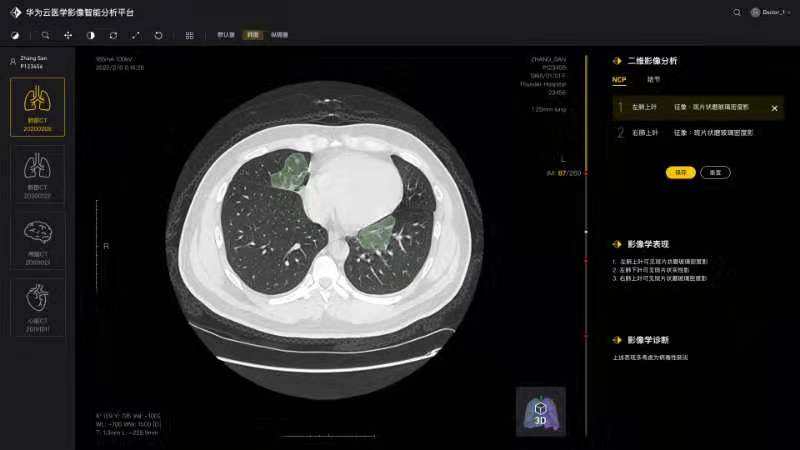

将论文写在祖国的大地上,加快加强疫情防控科研攻关,服务一线疫情防控救治——疫情发生以来,由学院白翔、许永超等老师负责的QY千亿球友会—华为智能创新实验室积极发挥自身优势,组织团队师生争分夺秒抓紧开展高质量科研攻关,与附属协和医院放射科、华为云、篮网科技等团队共同研发出一套基于人工智能技术的面向新冠肺炎肺部CT影像量化分析系统。2月29日下午,中共中央政治局委员、国务院副总理孙春兰率中央指导组来校考察疫情防控科研攻关情况,许永超副教授当场向孙副总理介绍了研发推出该系统的工作及成果。该系统可以辅助医生更高效地区分新冠肺炎的早期、进展期与重症期,有利于早期筛查与防控。同时,对于确诊病人,基于对多次复查影像数据的量化分析,医生能够有效评估病情进展及用药疗效等情况。目前该系统已在全国几十家医院使用,日均调用量3000多次。孙春兰肯定了研究团队所开发系统的精确性,可以辅助医生定量分析,大幅提升效率,缓解影像医生的压力。她非常关注该系统的落地应用情况,特别是在湖北省、武汉市的应用,鼓励团队结合CT影像与核酸试剂等信息,进行更为精准的新冠肺炎诊断。